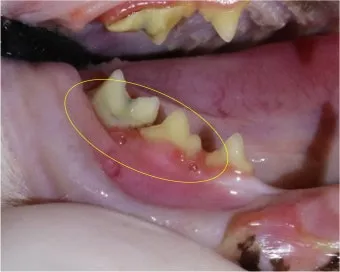

첫째, 치주 탐침 검사입니다. 치주 포켓 깊이를 밀리미터 단위로 재서 염증 범위를 가늠합니다.

둘째, 치과 방사선 촬영입니다. 겉으로 멀쩡해 보여도 치근 흡수나 농양이 숨어 있을 수 있어요. 촬영은 보통 10~20분 사이로 끝납니다.

셋째, 구강 내 사진 기록입니다. 치료 전후 비교와 모니터링에 필수입니다. 집에서도 사진을 주기적으로 찍어 병원에 보여주면 큰 도움이 됩니다.

고양이 치주염과 구내염, 치흡수성 병변은 겹치는 부분이 있습니다. 그러나 통증 위치와 병변 모양에서 차이가 보입니다.

구내염은 보통 구강 뒤쪽 아치의 넓은 발적과 심한 통증을 동반하고, 치흡수성 병변은 치경부가 움푹 파이거나 치관이 잘게 부서지는 양상이 특징입니다. 사진 기록이 큰 힘을 발휘합니다.